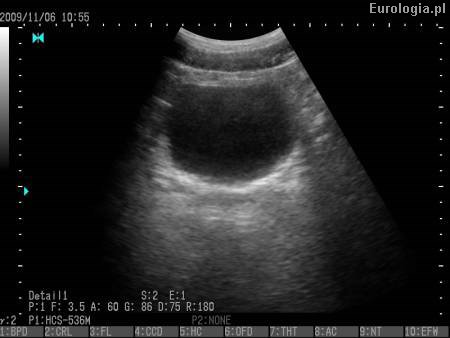

USG układu moczowego

Fot. Pęcherz moczowy - obraz USG.